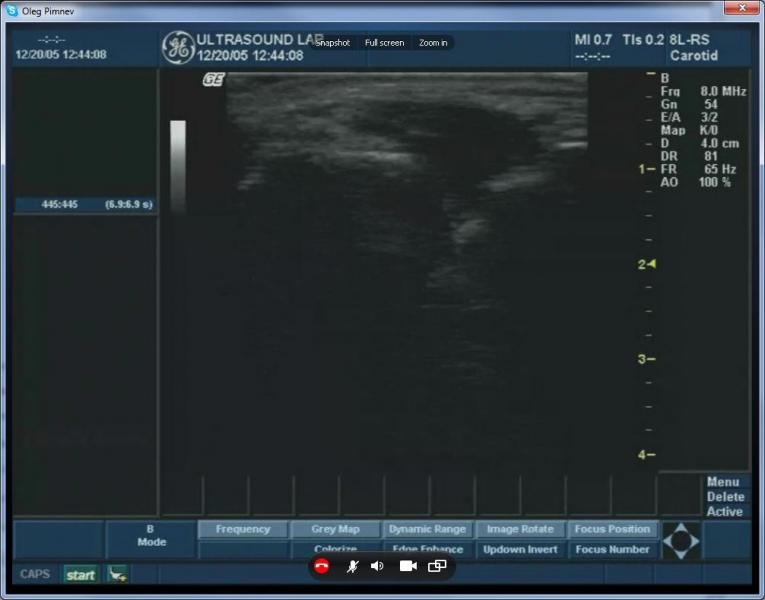

以下截圖是來自Skype超聲波圖像的廣播視頻:

在這個屏幕截圖、視頻從一個GE Logiq Book在網絡實時廣播到遠程參與者。

在上面的截圖中, 由于Skype視頻壓縮可以看到典型的色塊發生。不幸的是,因為Skype沒有視頻質量控制的選擇,沒有辦法擺脫他們。